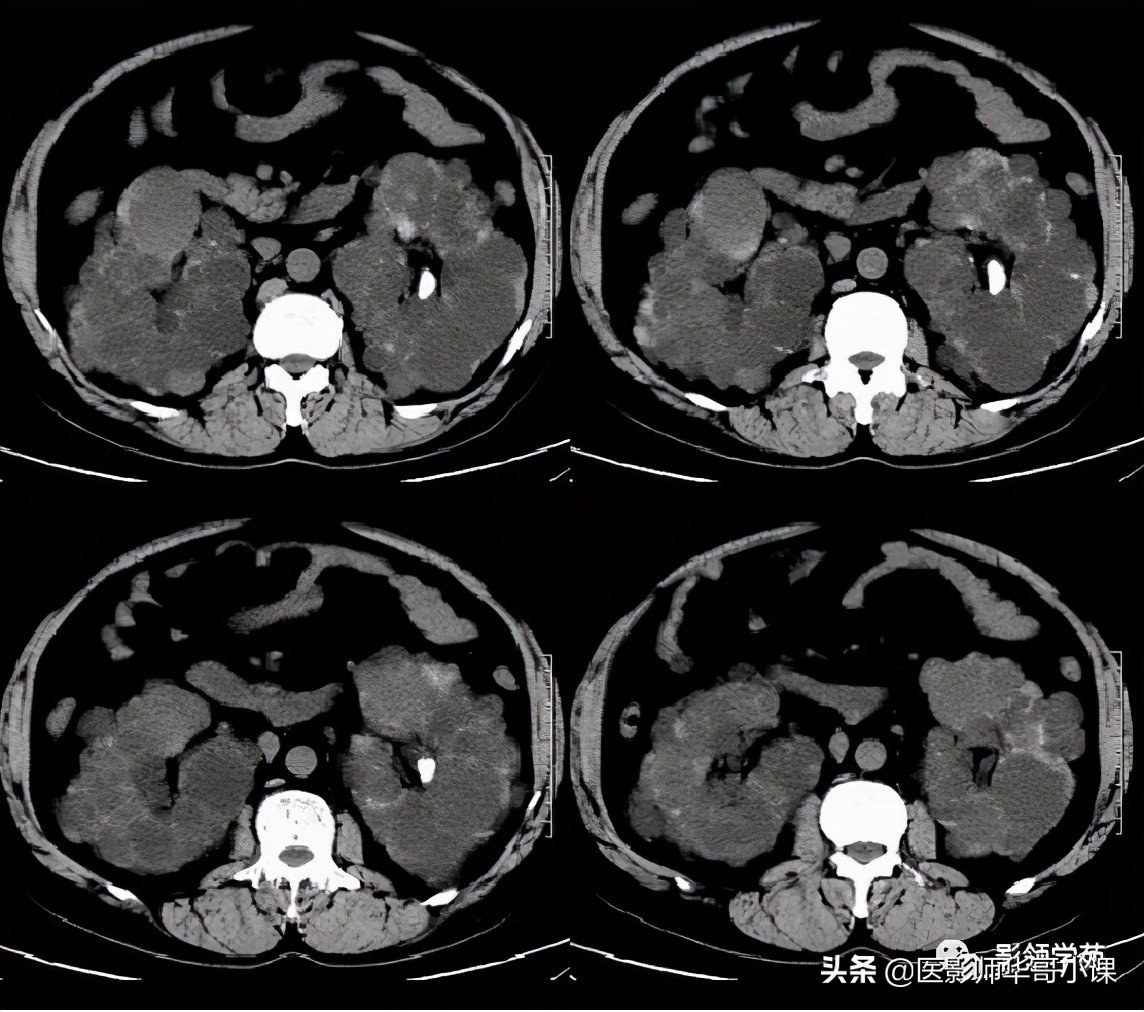

Caroli病影像诊断要点

1、肝内胆管不成比例的扩张,并与正常胆管相间,这是鉴别本病与继发性阻塞性肝内胆管扩张的关键所在,后者表现为从中央向末梢逐渐变细的、成比例的扩张。

2、“中心点征”是又一重要的征象,是指囊肿阴影内的小点状软组织影像,平扫密度等于或高肝实质,在T2WI序列上呈环状低黑信号,中央区呈圆柱稍高信号,其病理基础是门静脉分支被胆管扩张的囊壁包绕,并在切面上呈轴位投影。Seth等认为“中心点”征象的出现足准确的诊断本病。